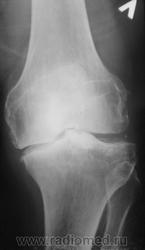

Как бы артроз, то артрозом, а дополнительное образование - костный фрагмент ?, инородное тело?, остеофит !? Он вообще сгибается?

Интереснейшая и редкая картинка! Первое впечатление, что это инородное тело в таком футляре из соединительной ткани. Валентин Львович, расскажите, будьте любезны, что же тут такое????

Инородного тела нет, не было травмы в ближайшее время. В настоящее время пациент находится в ОКБ, лежит в травматологии.

Да такой "футляр" ... десятилетия копится. Явно не в последние годы повреждение. Не вижу места, откуда бы оторвался фрагмент, и на остеофит явно не тянет. Очень любопытно, что на артроскопии... Если узнаете дальнейшие перипетии пациента, то отпишитесь, пожалуйста!

Пациенту в области делали толи КТ, толи МРТ сустава, точно не знаю, но он (пациент) еще не возвратился.